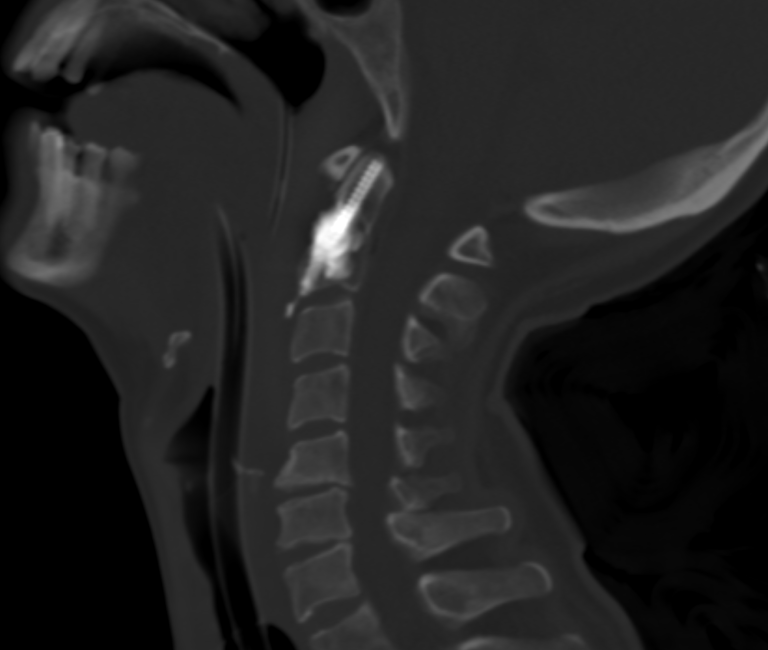

Consolider pour redonner de l’autonomie : une ostéosynthèse mini-invasive de la dent de la vertèbre C2

L’équipe de radiologie interventionnelle du CHU de Clermont-Ferrand a réalisé une première en Auvergne : une ostéosynthèse percutanée de la dent de C2 chez une patiente atteinte de cancer, présentant une lésion osseuse à haut risque de fracture.

L’ostéosynthèse de la dent de C2 par voie percutanée latéro-cervicale est une technique innovante, peu répandue en France et non réalisée jusqu’alors en Auvergne. Elle a été démocratisée par des équipes lyonnaises et parisiennes, et se distingue par son efficacité clinique et un faible taux de complications.

L’intervention se déroule en salle de radiologie interventionnelle, sous anesthésie générale. Grâce à un guidage scanner et scopique en continu, une précision millimétrique est assurée à chaque étape :

• Mise en place de la vis : introduction d’un trocart osseux, puis d’une broche et enfin d’une vis canulée adaptée à l’anatomie du patient.

• Cimentoplastie complémentaire : injection de ciment acrylique dans la lésion pour renforcer la consolidation et la stabilité de la vis.